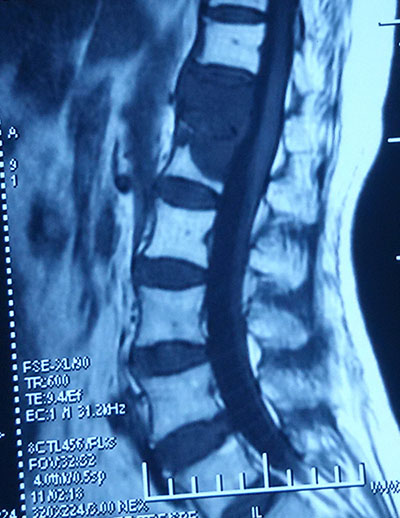

在我国人口老龄化过程中,骨质疏松性椎体压缩性骨折的病人逐渐增多,有资料表明,每年约有400万人因骨质疏松导致脊柱椎体压缩性骨折,其中170万以上的患者伴有药物难治性局部疼痛,约70万人因骨折引起的疼痛!畸形及合并症需要入院治疗,目前对于中老年骨质疏松性胸腰椎椎体压缩性骨折的治疗,除了相应的抗骨质疏松药物治疗以外,近年来国内外应用微创的办法通过椎弓根穿刺注射骨水泥对难治性疼痛性胸腰椎压缩骨折进行治疗,即所谓的椎体成形术。

椎体成形术是常用的微创技术是指经皮通过椎弓根或椎弓根外向椎体内注入骨水泥以达到增加椎体强度和稳定性,防止塌陷,缓解疼痛,经皮椎体后凸成形术还可以恢复椎体高度。在临床上广泛用于治疗椎体血管瘤,椎体转移瘤,和骨质疏松性椎体压缩骨折,取得了良好的止痛效果,它们良好的临床疗效和较高的安全性得到了广大医生和患者的认可,其不仅具有创伤小,手术时间短,出血量少等微创优点,还具有较好的复位作用,而且有迅速缓解疼痛,重建脊柱生物力学结构,恢复劳动力,提高患者的生活质量,不需要二次手术等优点.,尤其对于骨转移肿瘤患者可以有效的减轻疼痛,杀死部分肿瘤细胞,防止病理性骨折,第二天就可以下床行走,可以在提高生活质量同时,不影响马上放化疗。

以前的手术操作是在手工注射,医生吃射线,并且由于躲避射线影响操作,手工操作由于力量控制不好出现渗漏,注射不均匀等并发症,我们采取机械手操作,事先计算好注射量,硬度,医生在一边遥控指示下操作,使水泥能够在机械手操作下准确均匀注射,监视下更好控制注射量和速度,扩散更好,有效减少并发症提高疗效。该技术目前国内开展不多,豫北地区我们骨三科首先独立完成。